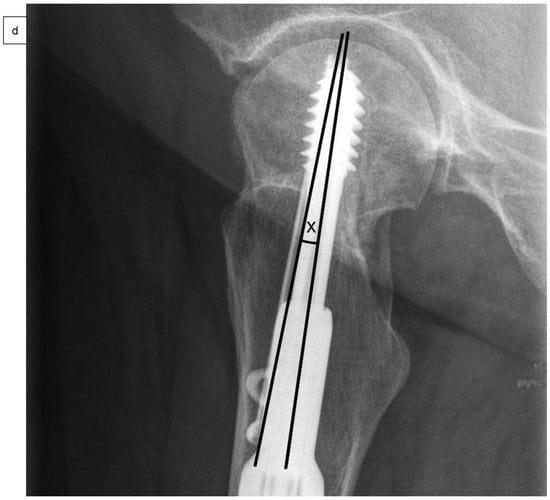

As well as epidemiological patient parameters and the Kellgren–Lawrence score at the time of hospital admission, the femoral neck angles (°) were captured in comparison to the opposite side (Figure 2a) after reduction and surgical stabilization six weeks postoperatively by using biplanar conventional radiographs. Valgus reduction was defined as a femoral neck angle of more than 5° in comparison to the opposite side. Then, the cohort group was divided into group “A”, which included patients with anatomical reduction, and group “B”, which consisted of patients with valgus reduction of the Garden type III femoral neck fracture. Further on, the angle of the 2- or 4-hole SHS plate (°), the tip-apex distance (mm) as described by Baumgaertner et al. (Figure 2b), and the angle between SHS and ARS (°) were measured in frontal (Figure 2c) and axial planes (Figure 2d) of the intraoperative or postoperative X-rays [].

Figure 2.

Measurement of the femoral neck angle (*) compared to the contralateral side (°), defined as the angle between the femoral neck axis and the bisecting line of the femoral shaft (a). The tip-apex distance (TAD) was defined as the calibrated summation of the distance between the tip of the SHS and the apex of the femoral head on anteroposterior and (not demonstrated) lateral radiographs (mm) (b), and the angle between SHS and ASR in the frontal plane (#) (c) and the axial plane (x) (d) by using biplanar conventional radiographs, six weeks postoperatively.